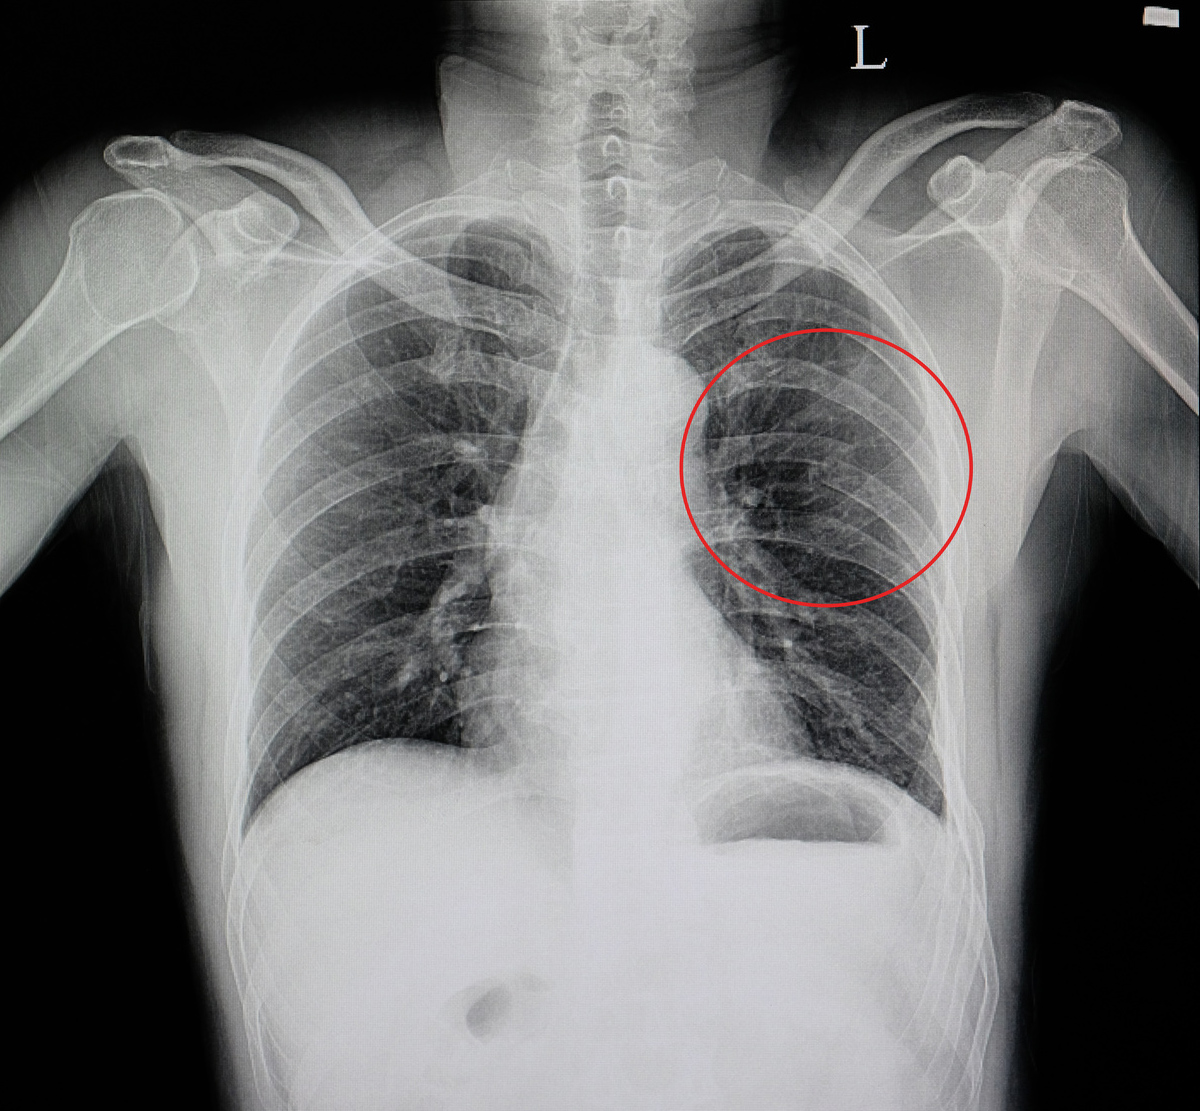

Złamanie żeber

Żebra chronią miękkie organy wewnętrzne takie jak serce czy płuca przed uszkodzeniem i urazem. Niestety, pomimo iż są one twardą tkanką kostną, mogą ulec stłuczeniu czy złamaniu na skutek urazów. Do najczęstszych przyczyn uszkodzenia żeber zaliczamy wypadki samochodowe, sporty kontaktowe czy mocne uderzenie. Żebra mogą również ulec złamaniom przeciążeniowym w trakcie wykonywania powtarzalnych czynności tj. pływanie, a także na skutek reanimacji, gdy zbyt mocny masaż serca powoduje ich uszkodzenie.

Ze względu na swoją ruchomość i czynny udział w oddychaniu, żebra nie mogą być unieruchamiane za pomocą sztywnych opatrunków gipsowych. Dlatego, w tym celu doskonale sprawdzi się nasz pas żebrowy OT-15, który delikatnie kompresuje klatkę piersiową, nie zmniejszając możliwości oddechowych pacjenta.

Żebra chronią miękkie organy wewnętrzne takie jak serce czy płuca przed uszkodzeniem i urazem. Niestety, pomimo iż są one twardą tkanką kostną, mogą ulec stłuczeniu czy złamaniu na skutek urazów. Do najczęstszych przyczyn uszkodzenia żeber zaliczamy wypadki samochodowe, sporty kontaktowe czy mocne uderzenie. Żebra mogą również ulec złamaniom przeciążeniowym w trakcie wykonywania powtarzalnych czynności tj. pływanie, a także na skutek reanimacji, gdy zbyt mocny masaż serca powoduje ich uszkodzenie.

Ze względu na swoją ruchomość i czynny udział w oddychaniu, żebra nie mogą być unieruchamiane za pomocą sztywnych opatrunków gipsowych. Dlatego, w tym celu doskonale sprawdzi się nasz pas żebrowy OT-15, który delikatnie kompresuje klatkę piersiową, nie zmniejszając możliwości oddechowych pacjenta.

Przeznaczenie

• przy złamaniach żeber, • przy złamaniach mostka, • przy stłuczeniach klatki piersiowej, • po operacjach kardiochirurgicznych, • w celu stabilizacji i wzmocnienia mięśni klatki piersiowej.Technologia